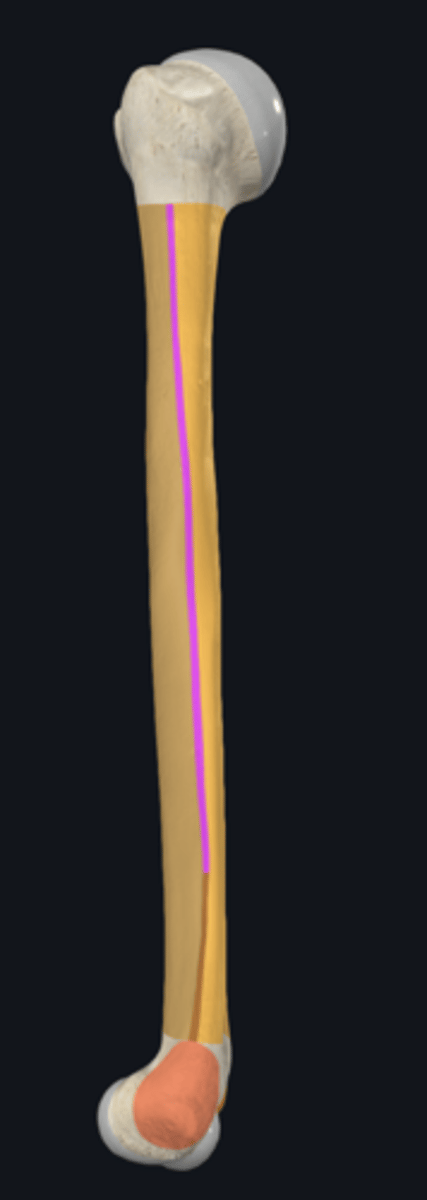

anatomical neck of humerus

body of humerus

condyle of humerus

greater tubercle

head of humerus

lesser tubercle

anterior border of humerus

anterolateral surface of humerus

anteromedial surface of humerus

lateral border of humerus

lateral epicondyle of humerus

lateral supracondylar ridge

medial border of humerus

medial epicondyle of humerus

medial supracondylar ridge

posterior surface of humerus

Capitulum

coronoid fossa

Crest of greater tubercle

crest of lesser tubercle

deltoid tuberosity

groove for ulnar nerve

bicipital groove

olecranon fossa

radial fossa

radial groove

surgical neck of humerus

trochlea